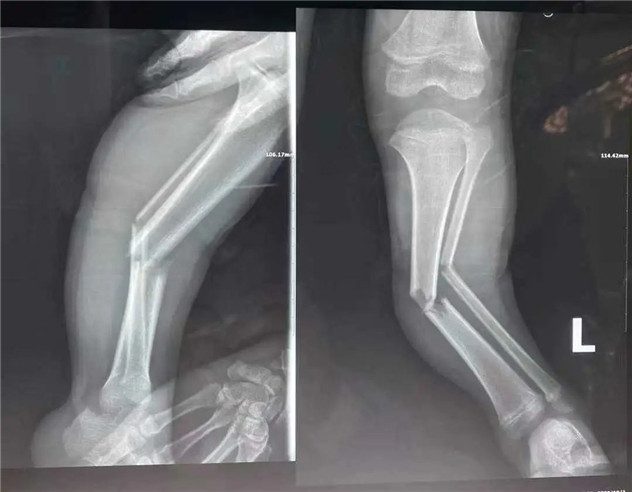

經(jīng)拍片顯示,睿睿左脛腓骨中段粉碎性骨折。接診的我院骨科中心主任羅軍建議其入院接受手術(shù)治療。

術(shù)前